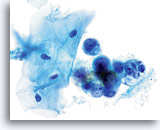

Carcinosarcome

Présence d’éléments glandulaires néoplasiques et de débris nécrotiques permettant d’établir un diagnostic de carcinosarcome.

60X